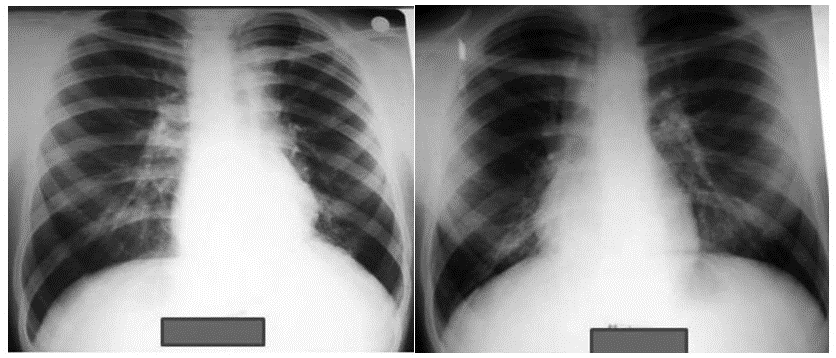

Chest X-rays of a 14-year-old male (BCG-vaccinated) with a positive tuberculin skin test and dextrocardia. Pneumonic infiltration was detected at the follow-up in the right lower zone of the chest X-ray after 50 days of isoniazid treatment

BCG (Bacille Calmette-Guérin) vaccine is a vaccine that is used to protect against tuberculosis. This vaccine is not widely used in the United States. However, it is often given to infants and small children in other countries where TB is common. It primarily affects the lungs but can also infect other parts of the body, such as the lymph nodes, bone, and brain.